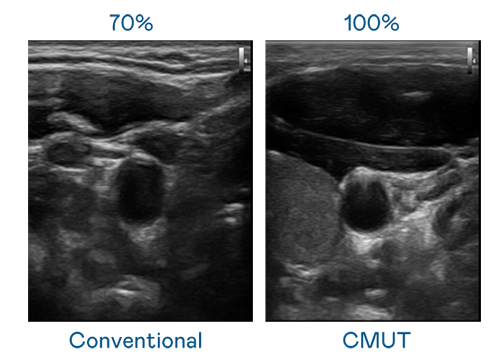

CMUT 技术是一种用电容式微机电元件来产生超音波讯号的技术。与传统 PZT 压电式技术相比,CMUT 频宽增加 30%,更宽频的超音波讯号让影像解析度大幅提升,是实现高影像品质医疗超音波扫描、促进精准医疗发展的关键技术。

超音波影像的解析度高低,首先取决于探头能发出的讯号频宽。AG真人 CMUT 可提供高清晰的超音波讯号,提供高频宽、高灵敏度、影像纹理细节更高的超音波影像,协助医护人员缩短影像判读时间及利用精准的医疗影像进行诊断。